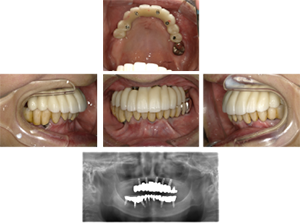

60代 女性 全顎 インプラント サイナスリフト等

| 年代・性別 | 60代・女性 |

|---|---|

| 主訴 | 上顎の入れ歯が割れた。リンゴやおかきを食べられるようになりたい。 |

| 部位 | 右上④3②・左上②3④5⑥のブリッジ |

| 治療期間 | 2年 |

| 費用 | ¥2,447,500(税込) |

| 副作用・リスク |

|